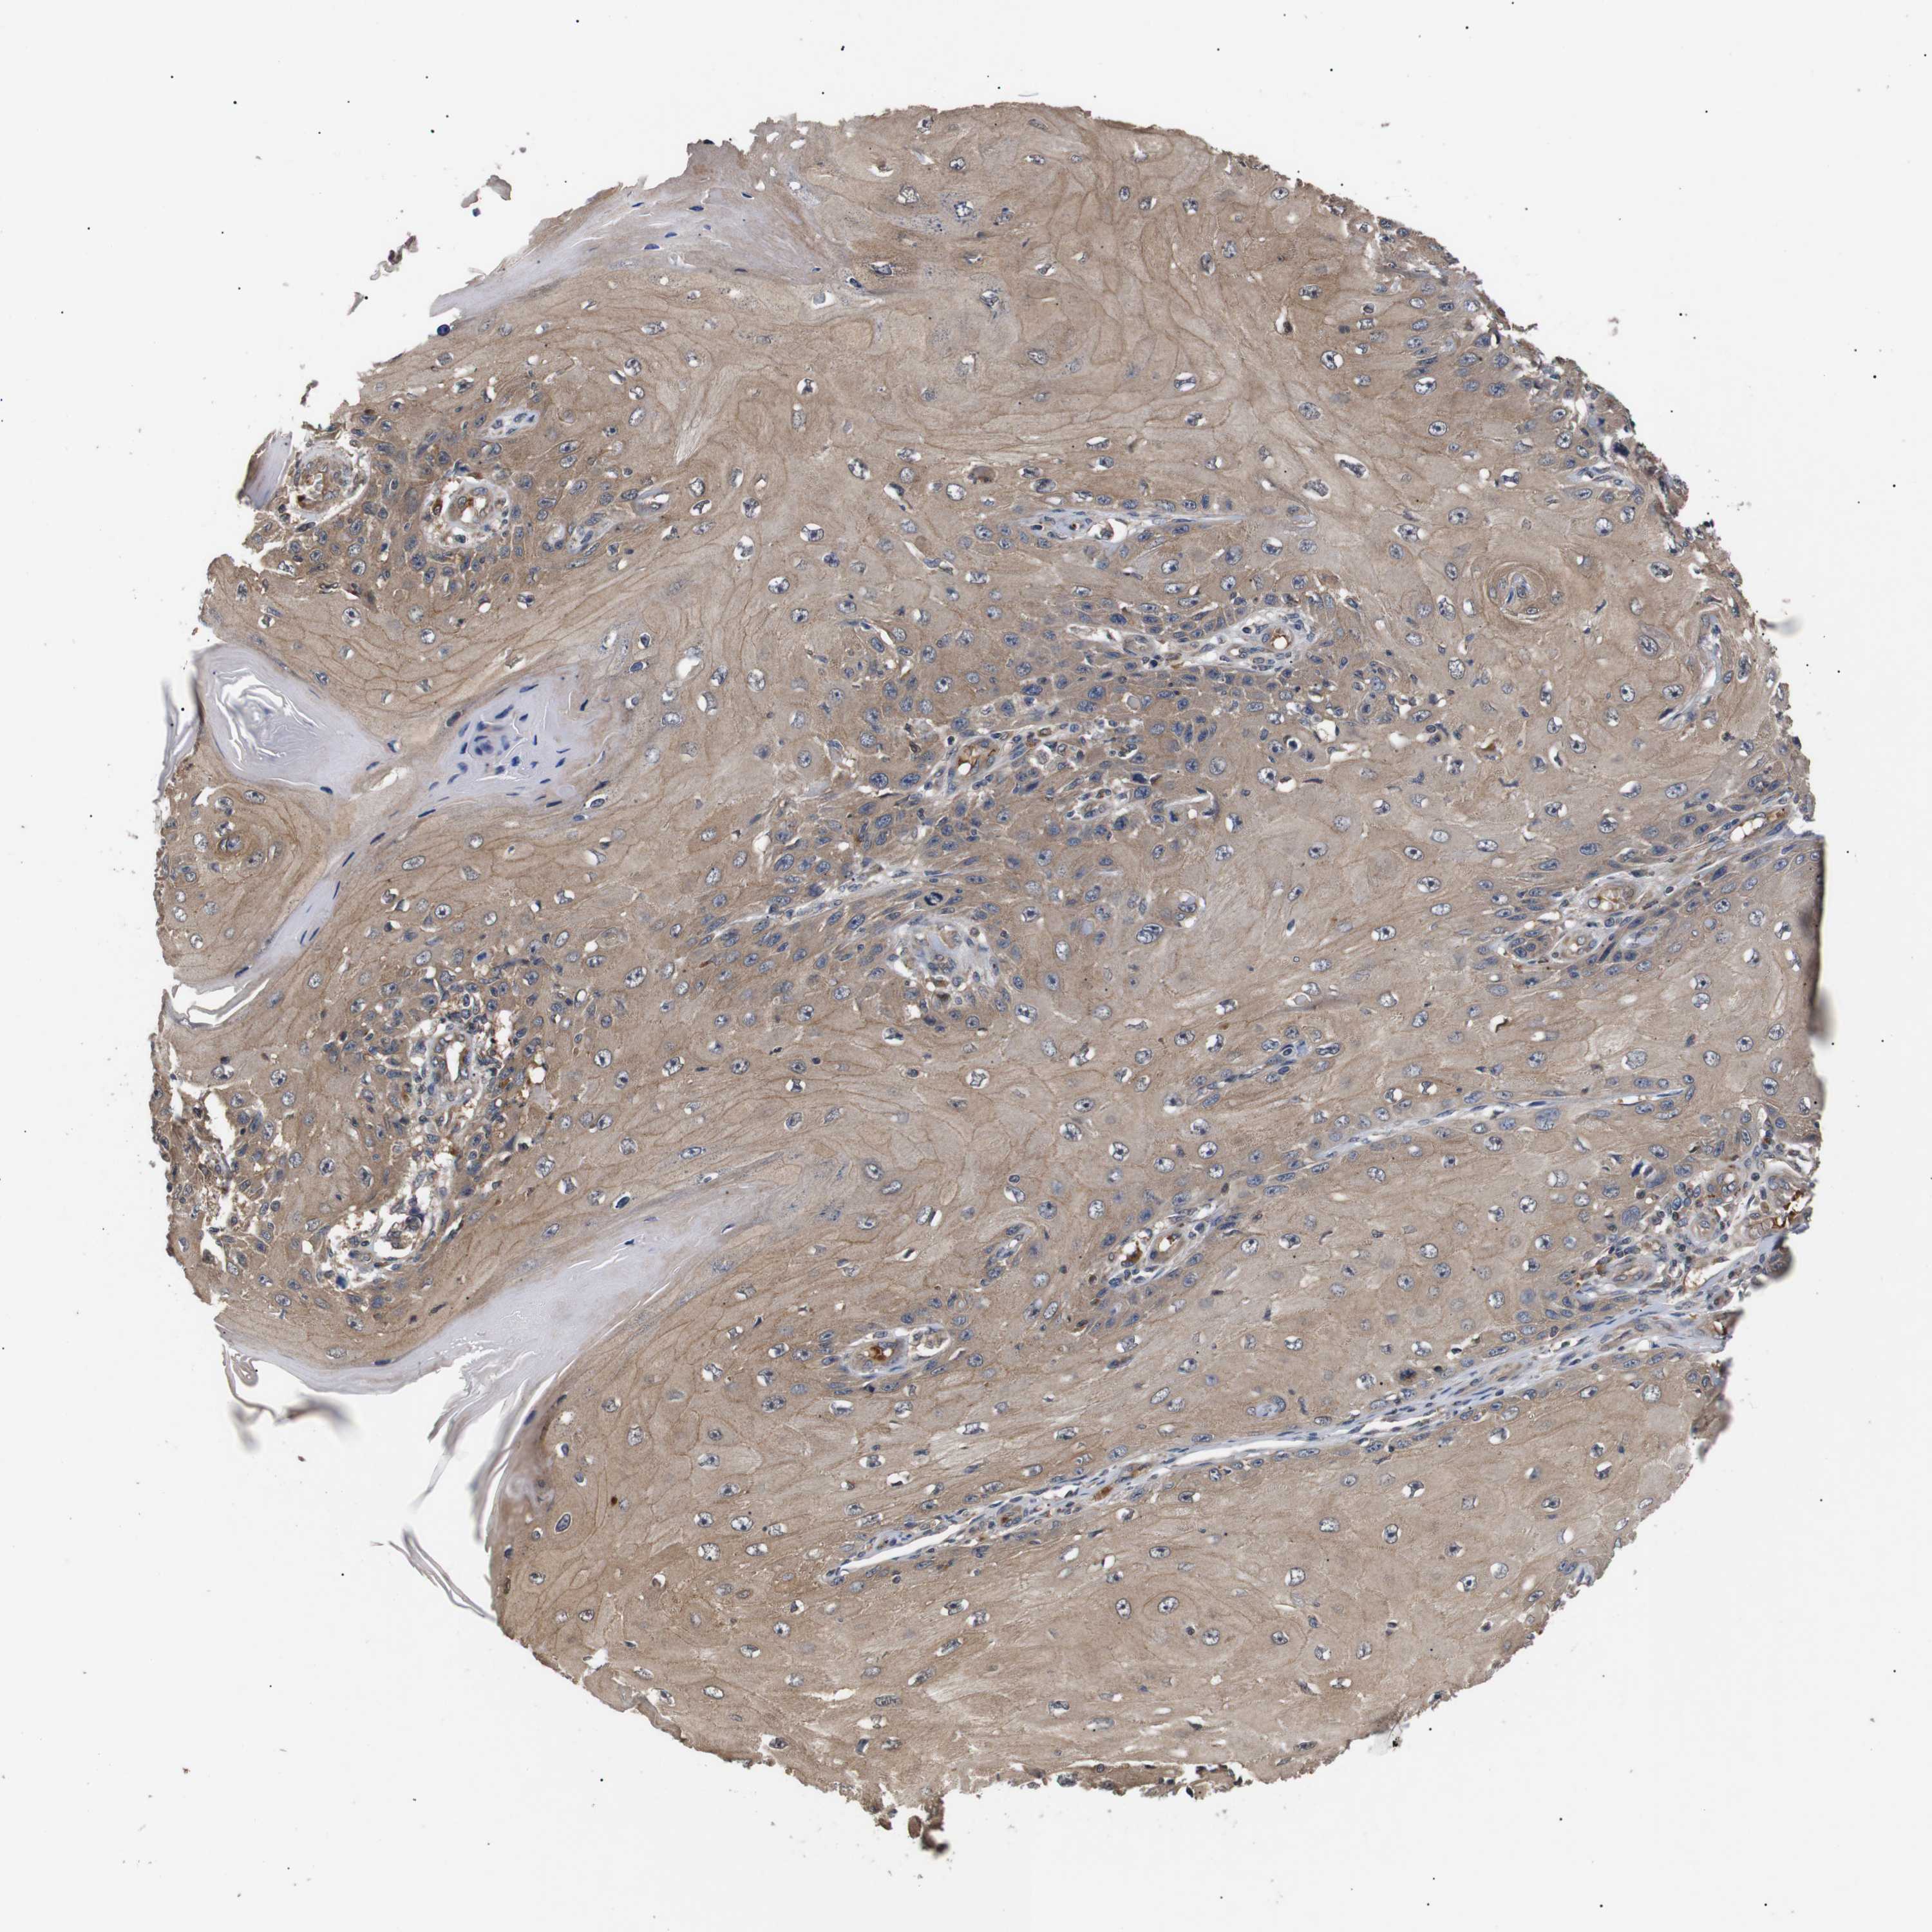

SKIN CANCER - Protein expressioni

A mouse-over function shows sample information and annotation data. Click on an image to view it in a full screen mode. Samples can be filtered based on level of antibody staining by selecting one or several of the following categories: high, medium, low and not detected. The assay and annotation is described here.

Antibody stainingi

Antibody staining in the annotated cell types in the current human tissue is reported as not detected, low, medium, or high, based on conventional immunohistochemistry profiling in selected tissues. This score is based on the combination of the staining intensity and fraction of stained cells.

Each image is clickable and will lead to virtual microscopy that enables deeper exploration of all samples and also displays staining intensity scores, fraction scores and subcellular localization as well as patient and tissue information for each sample.

Antibody CAB010162

Antibody CAB025656

Staining

High

Medium

Low

Not detected

Intensity

Strong

Moderate

Weak

Negative

Quantity

>75%

75%-25%

<25%

None

Location

Nuclear

Cytoplasmic/membranous

Cytoplasmic/membranous,nuclear

Squamous cell carcinoma, NOS

Basal cell carcinoma

Squamous cell carcinoma, metastatic, NOS